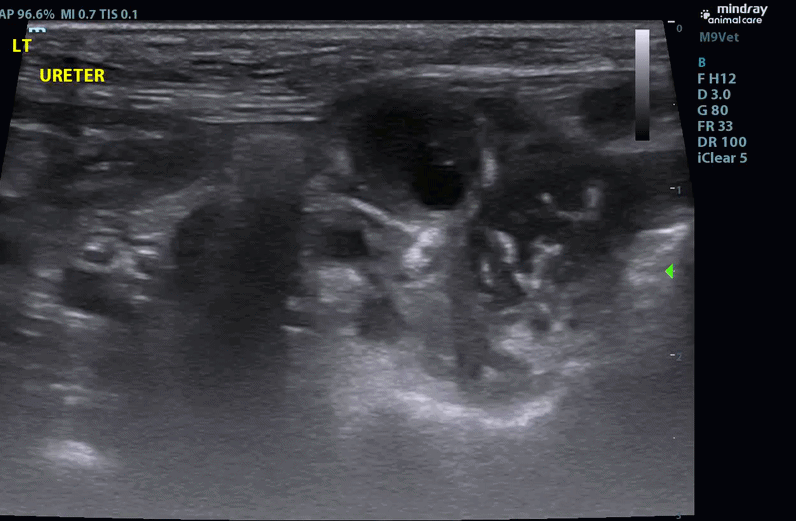

- Both ureters are mildly to moderately dilated along their length (Left - up to 4.3mm (decreased to 2.5mm at the level of the trigone); (Right up to 3.1mm - (decreased to 1.9mm at the level of the trigone)).

- The walls of the left ureter are mildly to severely and disproportionately thickened along its length (up to 5.0mm)

- Given the sonographic findings, partial obstruction of the ureters by the trigone mass with invasion of primary bladder neoplasia up the left ureter wall was most strongly suspected. The perinephric pseudocyst could have existed prior to bladder disease or could have developed secondarily which is considered more likely.